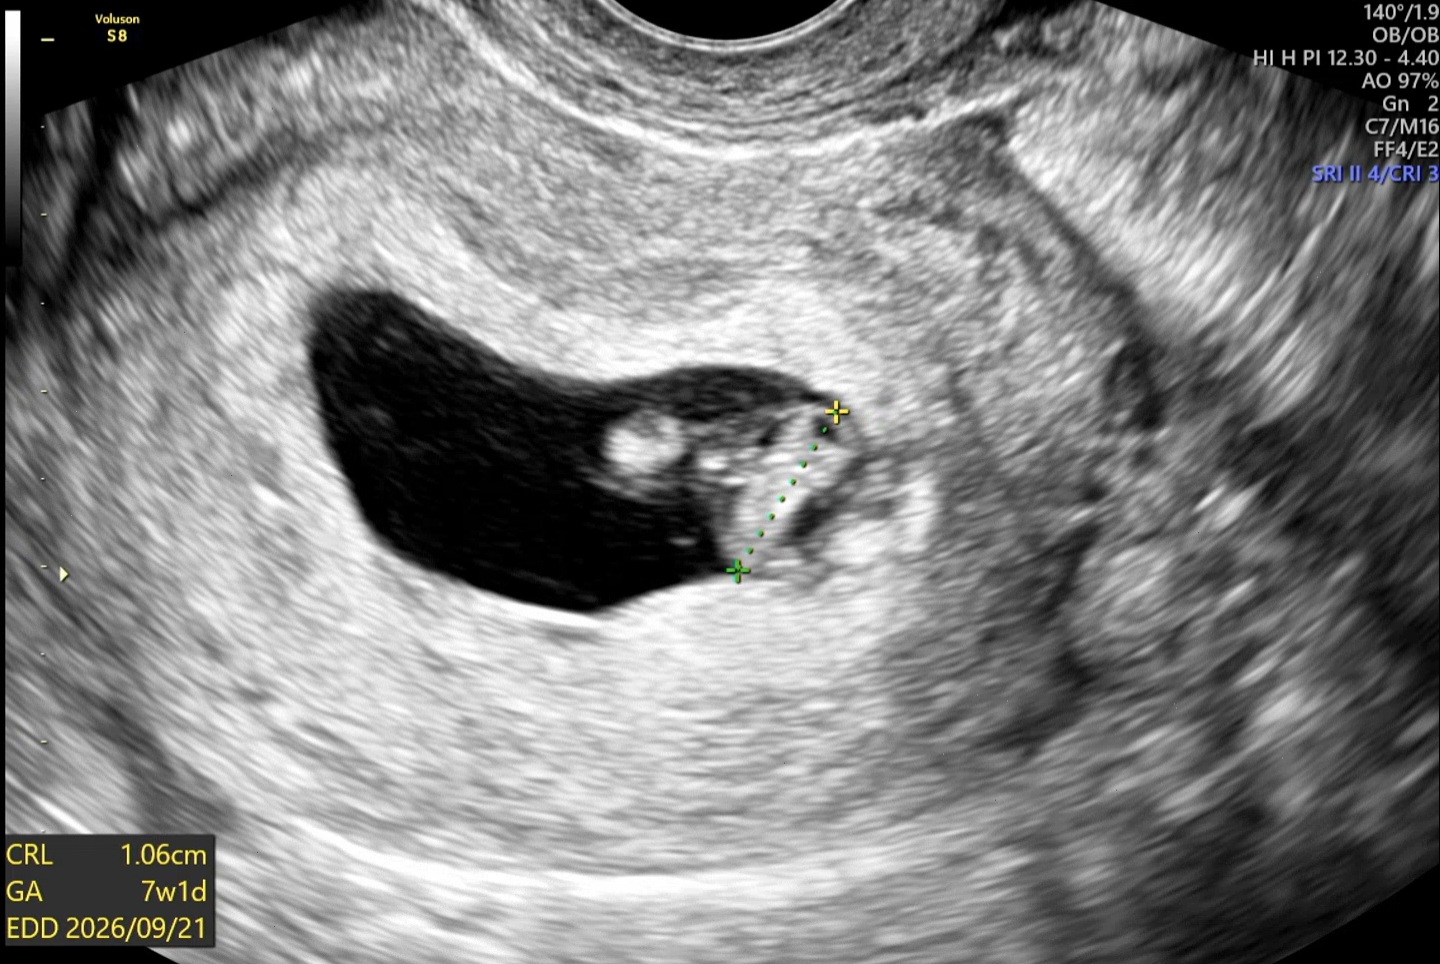

| 가슴 떨리는 임신 이야기를 공유해 주세요. | 유산 경험과 갑상선 절제 이력으로 걱정이 많았지만, 시험관 1차 시도에서 바로 착상에 성공하게 되었습니다. 여전히 조심스럽지만, 이번에는 진짜라는 느낌이 들어 설레고 기쁜 마음으로 하루하루를 보내고 있습니다. |

| 치료 도중 느꼈던 가장 기뻤던 순간과 절망적인 것들은 무엇인가요? 잊지 못할 경험이 있나요? | 가장 기뻤던 순간은 아기의 심장소리를 들었을 때였고, 가장 힘들었던 순간은 시험관 시도 전 인공수정을 준비했던 시간이었습니다. 길고 어렵게 느껴졌습니다. |